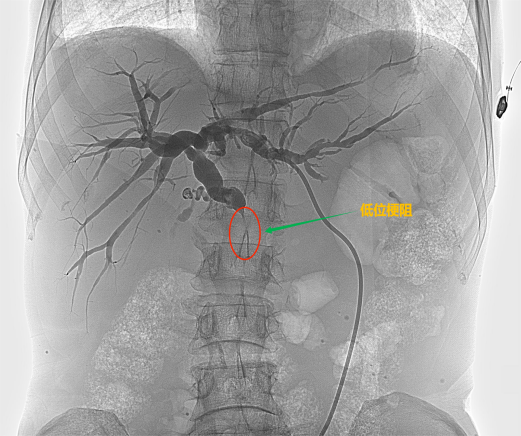

![]() 根据梗阻位置的不同可以分为低位胆道梗阻和高位胆道梗阻 ![]() ![]() ![]() 低位胆道梗阻 ![]() ![]() ![]() 高位胆道梗阻

![]() 【经皮胆道支架置入术】 ![]() 胆道支架置入能很好地弥补经皮肝穿刺胆道引流术的不足之处,通过在胆管狭窄/阻塞处安置金属支架,解除胆道梗阻、恢复通畅,促进胆汁入肠,改善消化功能的同时无需长期带管,显著提高了生活质量,适合短期内有效解除胆道梗阻的患者(如恶性胆道梗阻)。 ![]() 低位胆道梗阻支架置入 ![]() 高位胆道梗阻支架置入 变身“小金人”并不可怕,找准病因,用对方法,也能轻松退黄。介入治疗应用于胆道梗阻多年,技术成熟,安全且高效。市四医院介入室能常规开展各类复杂胆道梗阻的介入治疗,高效扫“黄”,为肝功能保驾护航。